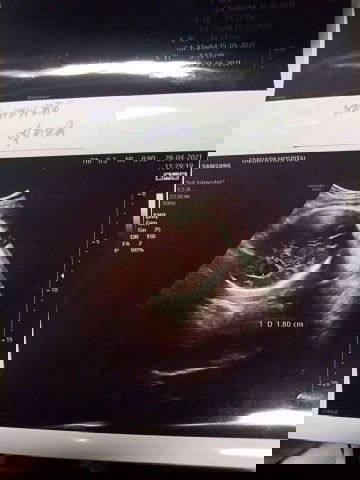

สอบถามค่ะ ไปอัลตร้าซาวตอน36w.หมอบอกว่าเด็กมีน้ำในโพรงสมองลูกมากกว่าปกติ จะเป็นอันตราหรือไม่ค่ะ😰

#ขอคำแนะนำหน่อยค่ะ #ท้องแรกคะ #ขอบคุณล่วงหน้านะคะ #ขอบคุณสำหรับคำตอบค่ะ #ใครมีประสบการณ์

สอบถามค่ะ

ไปอัลตร้าซาวตอน36w.หมอบอกว่าเด็กมีน้ำในโพรงสมองลูกมากกว่าปกติ

จะเป็นอันตราหรือไม่ค่ะ😰